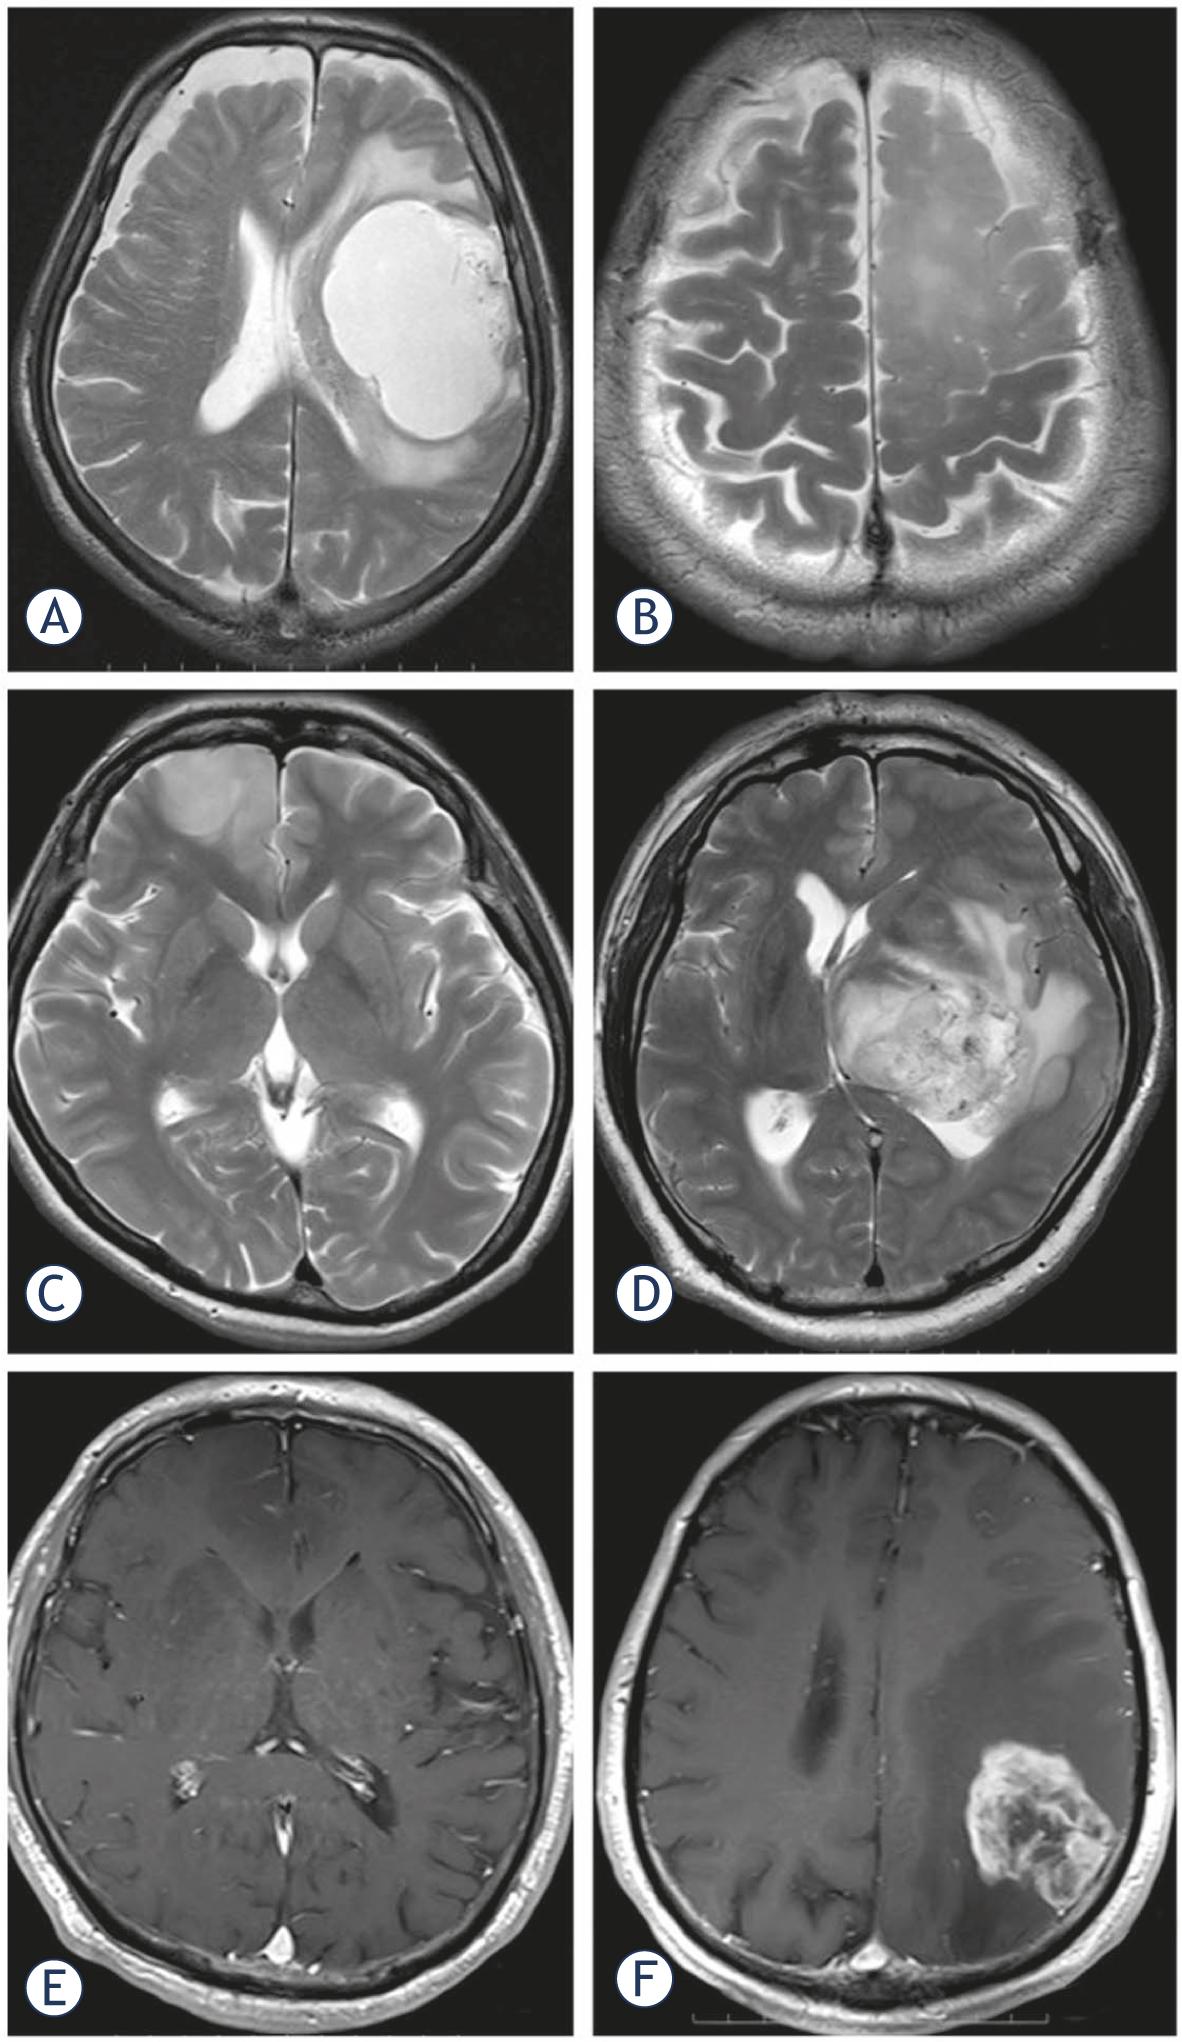

All preoperative MRI studies were performed within a week before surgery on a 3 Tesla scanner (Magnetom Verio; Siemens, Erlangen, Germany). T1- and T2-weighted- (T1W, T2W), and contrast-enhanced T1W axial images were used for analysis. The images were assessed consensually by two neuroradiologists blinded to the genotype and the 5-ALA-induced fluorescence of each lesion. They used methods described elsewhere21 to qualitatively assess the following findings: a sharp or indistinct tumor border, homogeneous or heterogeneous signal intensity throughout the tumor on T1W and T2W images, and the presence or absence of contrast enhancement on contrast-enhanced T1W images (Figure 1). Identification of the predominant characteristics of individual tumors was based on the readers’ judgment of the tumor border and signal heterogeneity.

Comparison of tumor characteristics on MRI scans. Axial T2W images showing a mass with (A) a smooth and (B) an indistinct tumor border in the left frontal lobe, (C) homogeneous intensity in the right frontal lobe, and (D) heterogeneous intensity in the left thalamus. Axial gadolinium-enhanced T1W images show that (E) the tumor lacks contrast enhancement in the right frontal lobe and is (F) contrast-enhanced in the left parietal lobe.